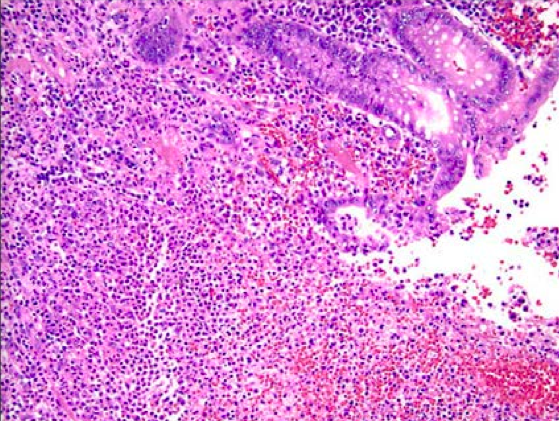

What are the genetic characteristics of this lesion?

Note the well-differentiated appearance of this squamous cell carcinoma. These involve loss of p53/p16 tumor suppressor genes and overexpression of RB.